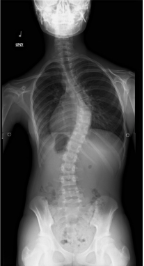

側弯症とは背骨がまがってしまう症状で、背骨のゆがみ、ねじれに伴い背中が隆起したり脊柱が弯曲する病気です。

前屈した時に肩・背中・腰の高さに左右差がある場合や、真っ直ぐに立った状態で肩の高さや肩甲骨の位置、ウエストラインに左右差がある場合などは側弯症を疑います。

構築性側弯症とは、椎体(背骨の一部)そのものが捻れたりや潰れるように変形します。

その中でも原因がはっきりしていない側弯症を「特発性側弯症」と呼び、側弯症全体の80~90%を占めるといわれています。